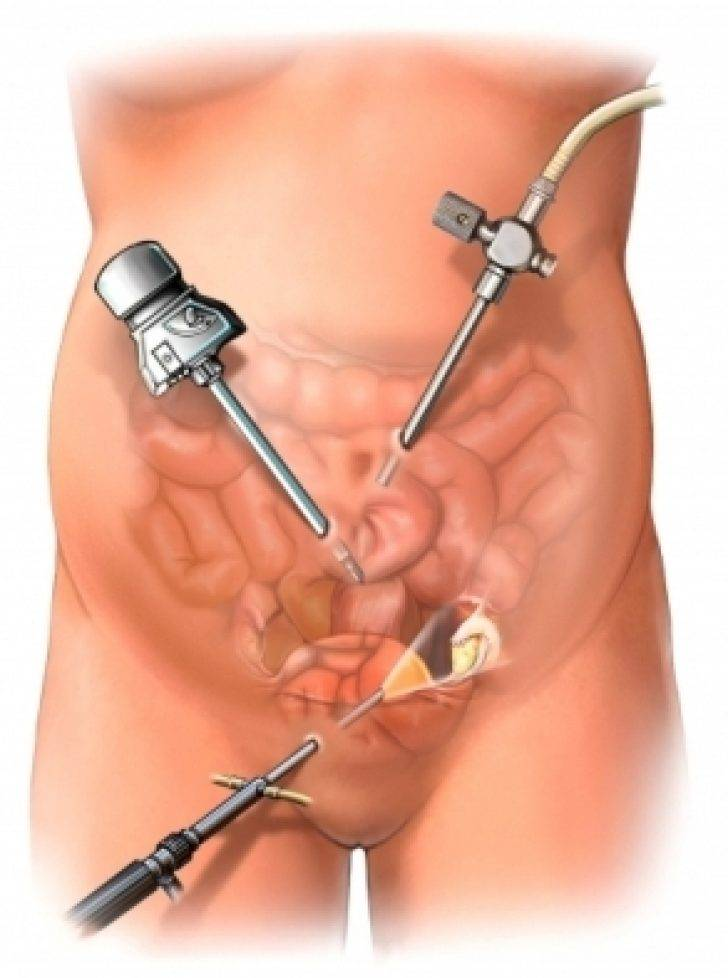

Современные методы лапаротомии и миомэктомии